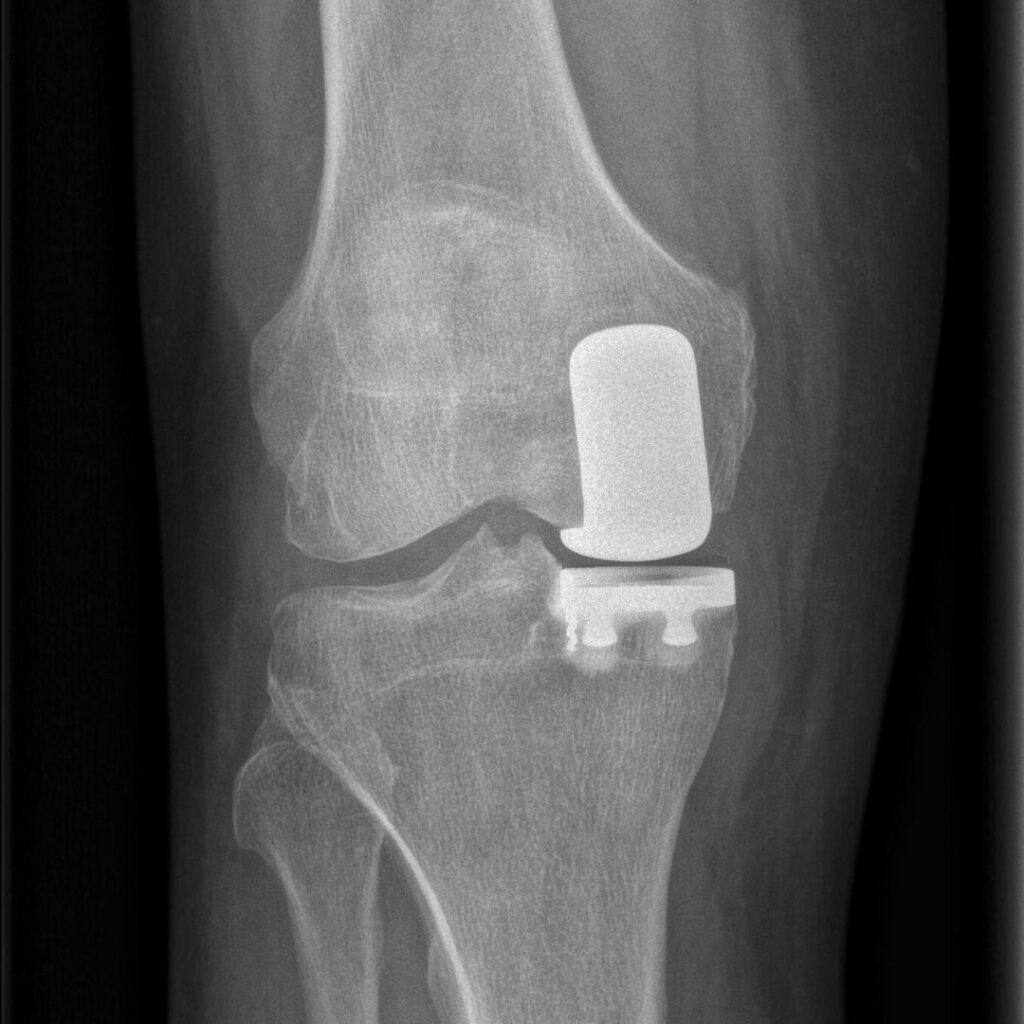

La protesi monocompartimentale di ginocchio è un intervento chirurgico che sostituisce soltanto la parte danneggiata dell’articolazione, preservando le strutture sane. Nel mio lavoro ho sempre considerato questa procedura la vera forma di chirurgia mininvasiva del ginocchio, perché consente di intervenire in modo selettivo, rispettando l’anatomia e la funzione naturale dell’articolazione.

L’indicazione principale è l’artrosi localizzata in un solo compartimento del ginocchio. L’articolazione del ginocchio è formata da tre compartimenti: mediale, laterale e femoro-rotuleo. Quando l’usura cartilaginea interessa solo uno di questi — nella maggior parte dei casi il mediale — e gli altri due restano integri, è possibile sostituire solo la parte danneggiata senza coinvolgere l’intera articolazione. La protesi monocompartimentale è indicata anche in caso di osteonecrosi del condilo femorale o dell’emipiatto tibiale.

Le componenti protesiche, in lega di cromo-cobalto e polietilene, vengono fissate con cemento chirurgico, che garantisce stabilità immediata e un’ottima adesione all’osso. L’intervento dura in media meno di un’ora e comporta una perdita di sangue molto inferiore rispetto a una protesi totale. In molti casi il paziente può essere dimesso dopo 48 ore e iniziare la riabilitazione già il giorno successivo.

A differenza della protesi totale, che richiede la sostituzione completa delle superfici articolari e talvolta la resezione dei legamenti crociati, la protesi monocompartimentale consente di mantenere intatti i legamenti e la cinematica naturale dell’articolazione. Questo si traduce in un movimento più fisiologico e in una sensazione articolare più naturale.